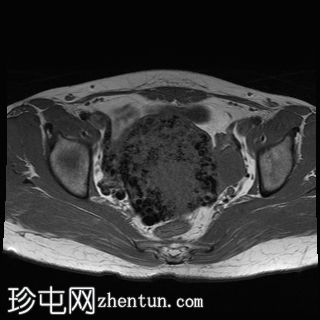

轴位

T2加权像

子宫增大且体积较大。扩张的血管主要位于子宫后壁(符合子宫动静脉畸形)。

子宫内膜肌层交界处也存在异常。

子宫内膜腔显影清晰,外观正常。